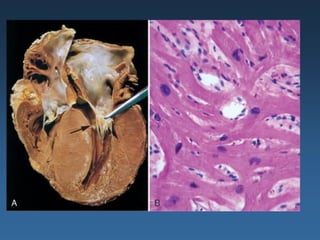

1- Raio x de Tórax:

Cardiomegalia acentuada.

2

2- Cardiomegalia com dilatação e

moderada hipertrofia .

1                  Trombos intracavitários.

3- microscopia:

3

a) fibrose difusa

b) infiltrado linfoplasmocitário

b                 e edema discreto.

a               c      c) edema intersticial

Microscopia

Fibrose intersticial.

Hipertrofia dos miócitos, que

possuem núcleo proeminente.